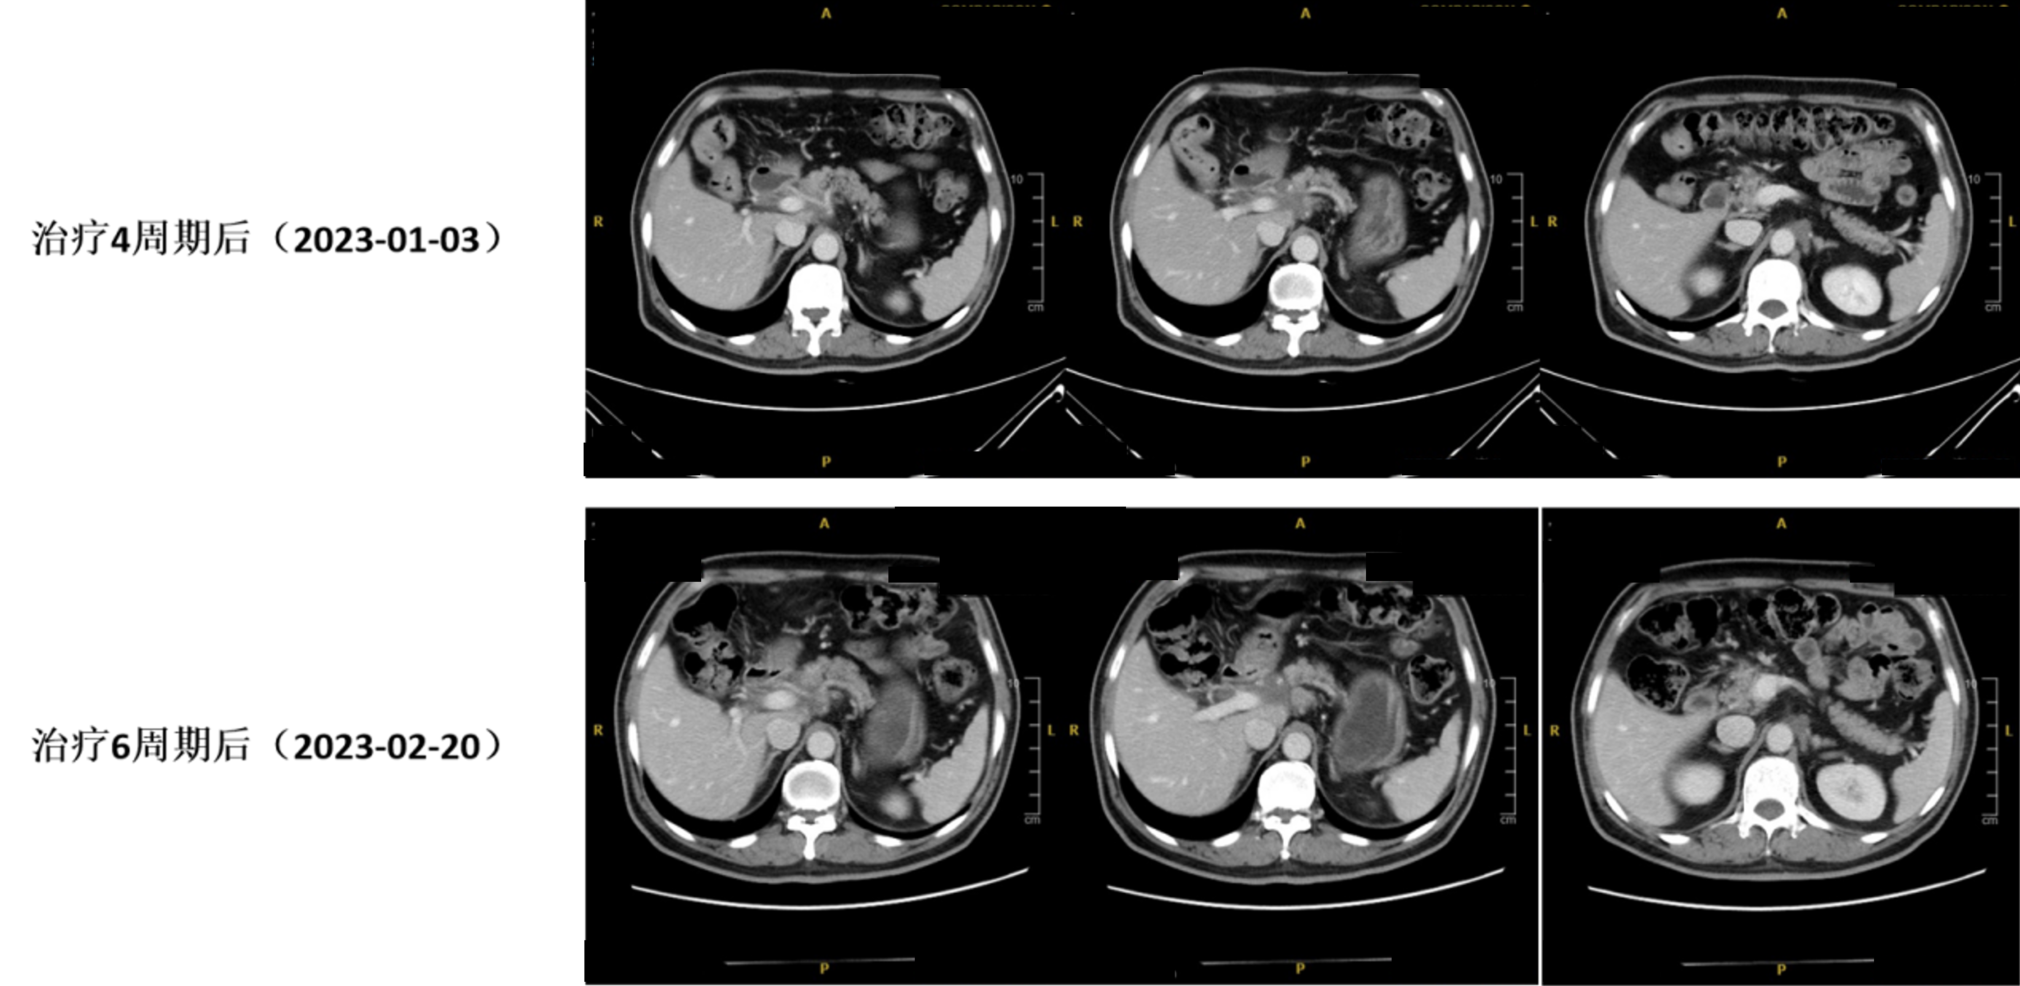

4周期治疗后疗效评估(CT复查:2023年01月03日): 胃窦胃壁稍增厚,较前变化不大;胰腺颈部病灶较前稍退缩;腹腔、腹膜后多发肿大淋巴结较前稍缩小。

6.jpg

图3. 治疗2周期后(2022年11月10日)与治疗4周期后(2023年01月03日)CT对比

6周期治疗后疗效评估(影像复查:2023年02月20日):

胸腹CT:胃窦胃壁稍增厚,较前变化不大。胰腺颈部病灶较前稍退缩,腹腔、腹膜后多发肿大淋巴结较前稍缩小。

7.jpg

图4. 治疗4周期后(2023年01月03日)与治疗6周期后(2023年02月20日)CT对比